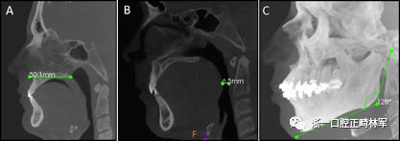

使用CS 3D成像軟件(版本3.4.3; Care-stream Health,Rochester,NY)進(jìn)行線性和角度測(cè)量。線性指標(biāo)包括鼻前后棘間距(ANS-PNS距離),咽腔最短距離(最短距離),咽腔C1的前后距離(APC1),咽腔C1的側(cè)壁間距離(LLC1),咽腔C2的前后距離(APC2),咽腔C2的側(cè)壁間距離(LLC2),咽腔C3的前后距離(APC3),咽腔C3的側(cè)壁間距離(LLC3),咽腔-會(huì)厭基底的前后距離(AP會(huì)厭),咽腔-會(huì)厭基底的側(cè)壁間距離(LL會(huì)厭),下頜骨兩側(cè)間的距離(L下頜骨),下頜骨的前后距離(AP下頜骨),舌骨兩側(cè)間的距離(L1舌骨)以及舌骨的前后距離(AP舌骨)。下頜骨前后角度的測(cè)量(下頜AP角),下頜橫角(TA下頜骨)和舌骨橫角(TA舌骨)。測(cè)量結(jié)果列于表I和圖1-4中。

圖1. A,ANS-PNS距離; B,最短距離; C,下頜AP角。

圖2. A,LLC1和APC1; B,LLC2和APC2; C,LLC3和APC3; D,LL會(huì)厭和AP會(huì)厭。

圖3.A,舌骨橫角; B,LL舌骨; C,AP舌骨。

圖4. A,下頜橫角; B,LL下頜骨; C,AP下頜骨。

為了進(jìn)行線性測(cè)量,所有CBCT檢查都根據(jù)要測(cè)量的結(jié)構(gòu)進(jìn)行定向。對(duì)于咽腔,垂直參考線位于正中矢狀面內(nèi),水平線在前鼻棘和后鼻棘的軸向和矢狀重建之中。對(duì)于下頜骨,水平線在矢狀重建中切向定位在下頜骨的下緣,然后向上移動(dòng)至頦結(jié)節(jié)。對(duì)于舌骨,軟件定位線在矢狀重建中定位在該骨的長(zhǎng)軸上。